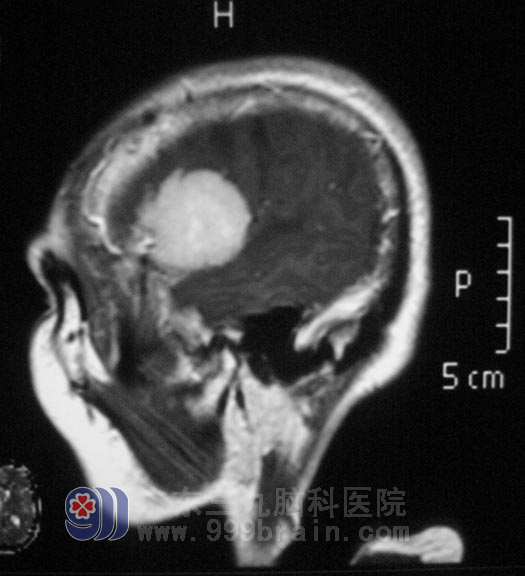

年近七旬的林奶奶一向身体很好,三天前突然出现头痛、头晕,双下肢乏力行走困难,在当地医院行头颅MR检查,结果提示右侧颞部占位。

入住广东三九脑科医院综合神经外科,完善相关检查后,鲁明主任主刀在全麻下行右侧颞部占位切除术,术中导航定位,显微镜下见肿瘤呈红白色,质地中等,血运一般,与脑组织边界较清,予镜下行肿瘤全切。病理结果为:混合型脑膜瘤 WHO I级。经过治疗,林奶奶行走如初,没有任何后遗症。